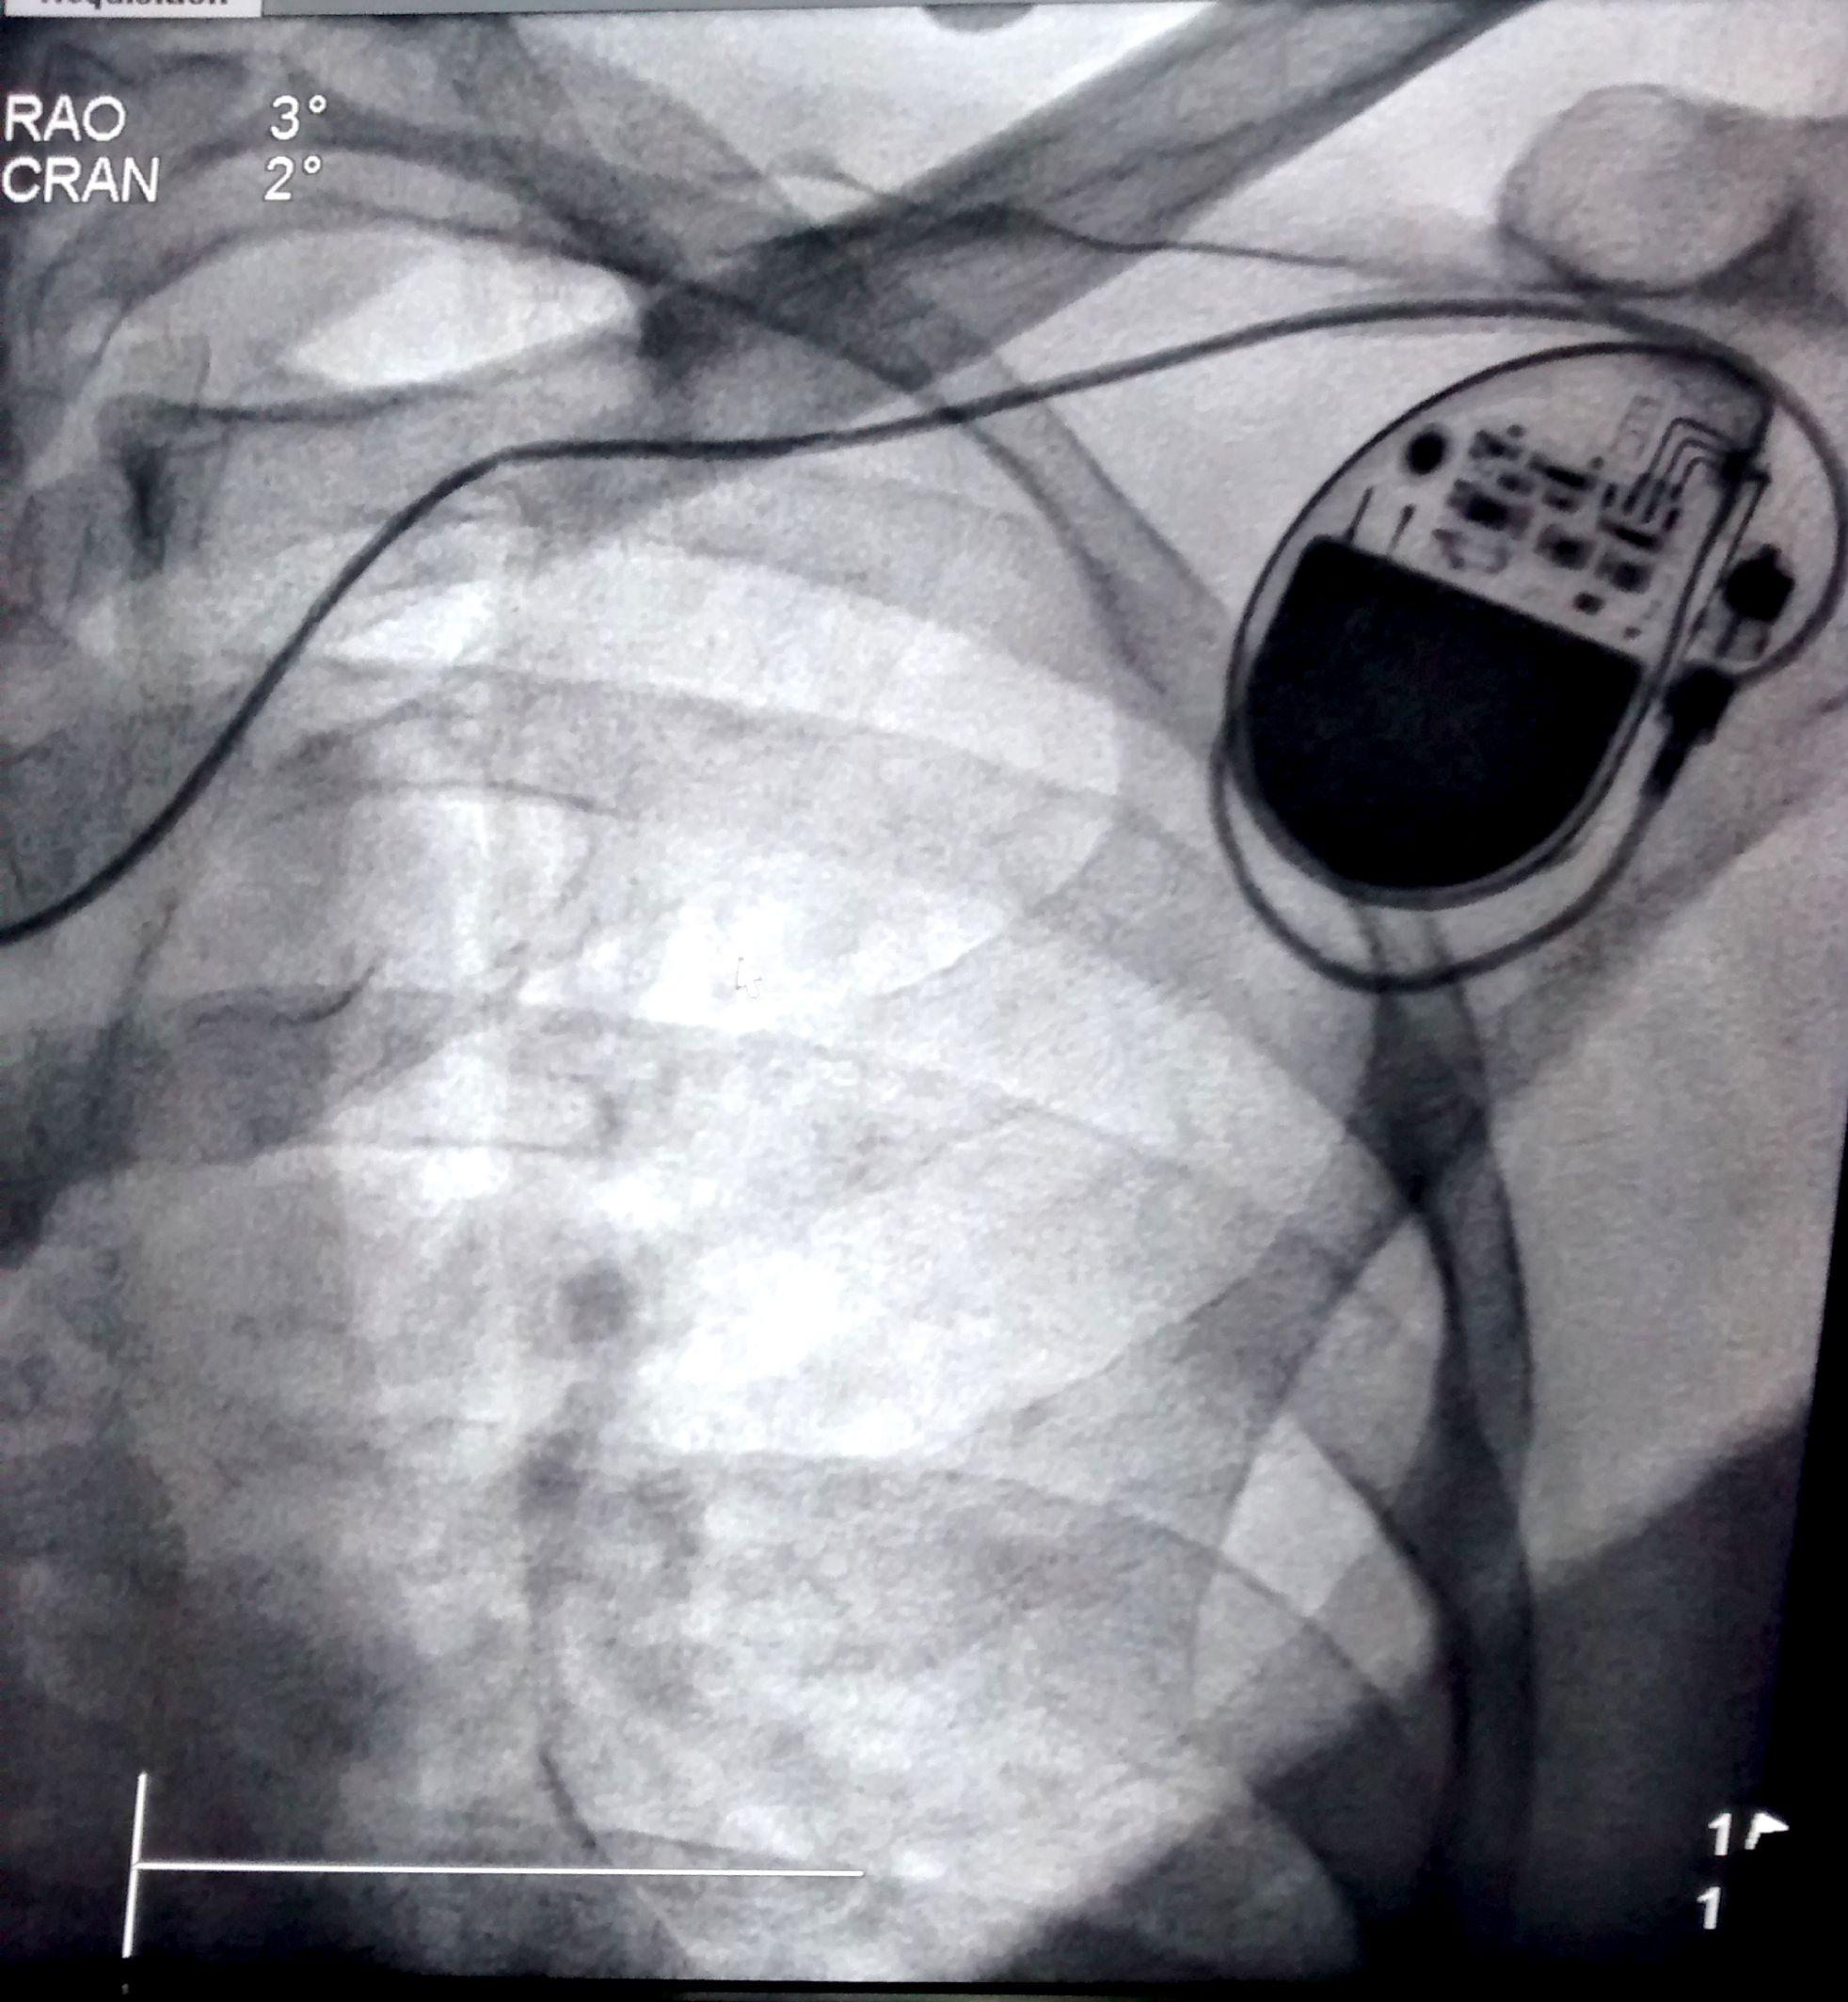

Lead crush

subclavian_crush.jpg